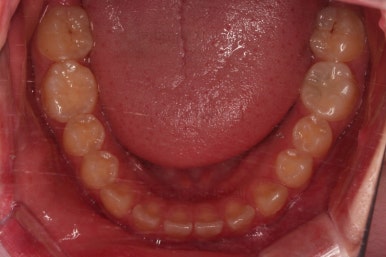

동래교정치과 초진 시 입안의 모습입니다.

치아가 벌어진 것도 벌어진 것이지만 교합이 전혀 안되고 있었어요.

틈새도 아랫니에 훨씬 많았고요.

윗니가 있는 위턱뼈가 전반적으로 아래턱에 비해 3차원으로 작은 양상이었습니다.

이번 환자분은 아랫니가 전반적으로 앞이든, 뒤든, 양옆으로든 넓어져 있는 양상이었고 그래서 아랫니에 틈도 많고 아래 앞니도 밀려나와 있는 양상인거죠.

전후 사진을 비교해 볼게요.

악궁확장을 통해 위아래 악궁의 크기 조화를 맞췄고, 틈새도 모았으며 교합도 적절히 마무리를 했습니다.